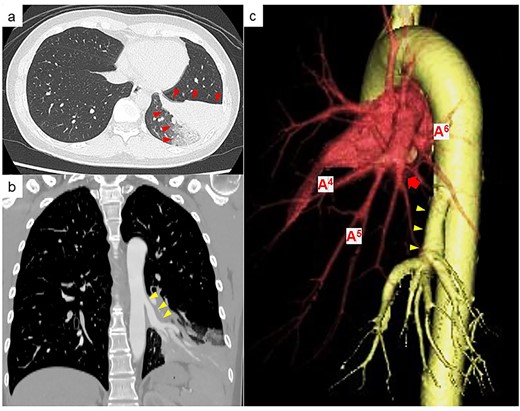

A 39-year-old female, who typically experienced a small amount of haemoptysis about once a year was referred to our hospital because of a new case of severe haemoptysis. Chest computed tomography (CT) showed a pulmonary infiltrative shadow because of haemorrhage in part of the left basal lung segments (Fig. 1a). An anomalous artery branching from the descending aorta into the left basal lung and the position of the bronchus at the normal branch were observed, suggesting an ABLL (Fig. 1b). Three-dimensional CT showed the distribution of blood flow within the left lower lobe was divided between the original atrophic basal part of the pulmonary artery and the anomalous artery (Fig. 1c). While haemoptysis improved with conservative treatment, she requested surgery, which was performed 7 months following severe haemoptysis onset. Written informed consent was obtained from the patient.

(a) Chest CT at the time of haemoptysis showing a pulmonary infiltrative shadow because of haemorrhage in part of the left basal lung segment (red arrowheads). (b) Contrast-enhanced CT showing an anomalous artery branching from the descending aorta (yellow arrowheads). (c) Three-dimensional CT showing that the original basal part of the pulmonary artery is atrophic (red arrow), and the basal part of the pulmonary artery and anomalous artery (yellow arrowhead) is clearly separated in the distribution of blood flow within the left lower lobe.